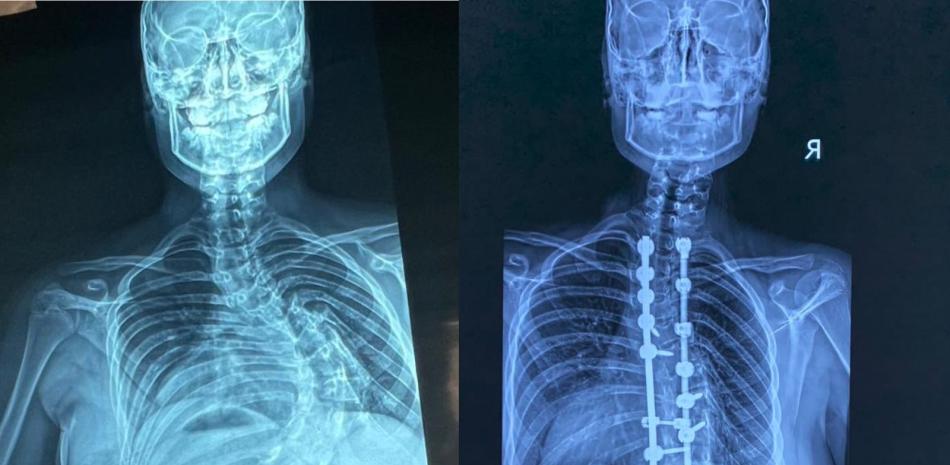

Unas 350 cirugías de corrección de deformidades de columna vertebral pediátrica se han realizado en República Dominicana, en los últimos cuatro años, en el hospital Robert Reid Cabral y la Sociedad Dominicana de Rehabilitación, coordinadas por el doctor Carlos Rodríguez Estévez, presidente de la Sociedad Dominicana de Cirugía de Columna.

En el Hospital Infantil Robert Reid Cabral se realizaron más de 250 procedimientos, mientras que 100 cirugías corresponden a la Sociedad Dominicana de Rehabilitación, cifra alcanzada en este año 2026.

La escoliosis es una desviación de la columna vertebral mayor de 15 grados. El especialista detalló que la forma más frecuente es la idiopática del adolescente.